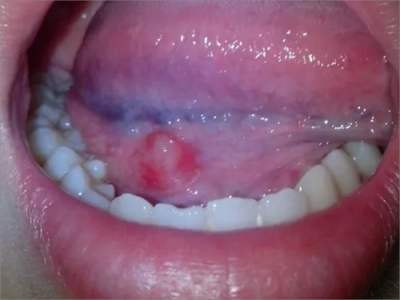

舌下腺囊肿舌头下面右侧有一个紫色包块图

舌下腺囊肿出现在口底舌系带一侧,表现为紫蓝色的隆起性包块,形态大致呈球形,界限清楚,质地柔软,囊肿增大后因破裂流出黏液。